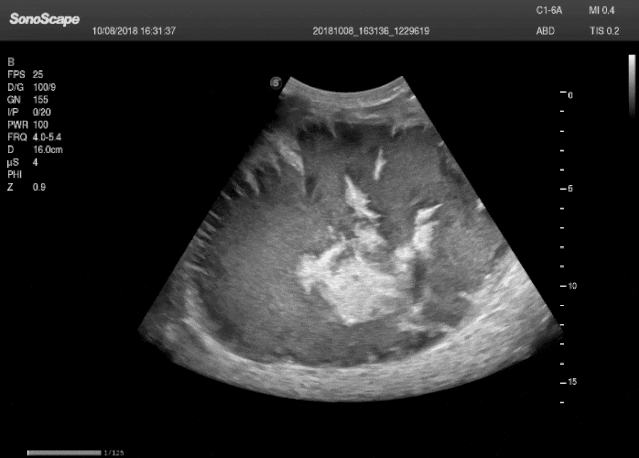

图 基于机器人超声检查(Robotic Ultrasound System, RUSS)的LUS场景:(a) RUSS的设置和坐标约定。(b) 超声探头的放置位置以获取纵向肋间视图,即LUS的SIP。(c) 从SIP获取的代表性超声图像。(d) 探头的平面内视图和平面外视图。红色光束代表光学传感器的距离测量。